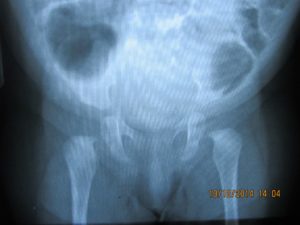

Если тазобедренный сустав имеет связанную с развитием ядра патологию, ее обнаружит УЗИ. Для ее выявления применяют и методы сонографического исследования. Часто может потребоваться и рентгенологическое исследование таза. Рентгеновский снимок для этого выполняется в прямой проекции.

Он дает возможность врачам получать максимально точную информацию о наличии или отсутствии патологии.

Патология ядра выявляется при помощи ультразвукового и сонографического исследования. Дополнительно проводится рентген поврежденных суставов таза. Для рентгеновского снимка выбирается прямая проекция, благодаря чему врачи могут получить более точную и подробную информацию о состоянии опорно-двигательного аппарата ребенка.